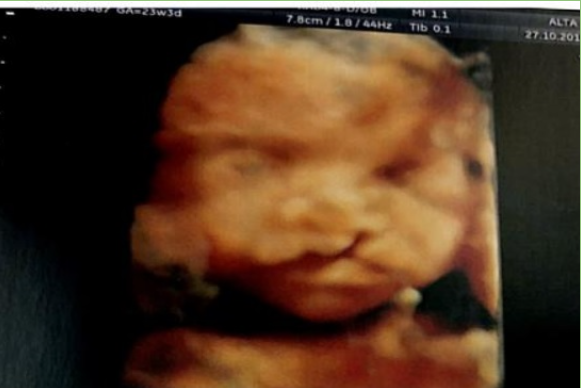

O diagnóstico durante a gestação é realizado através de exame de ultrassonografia e permite preparar os pais em relação a mal formação e consequente educação para as etapas futuras.

No momento do diagnóstico da fissura labiopalatina durante o pré natal é fundamental que o profissional responsável por esse diagnóstico tranquilize os pais, explique brevemente sobre a mal formação e encaminhe os futuros pais para atendimento especializado.